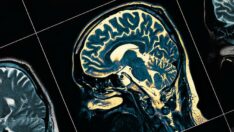

08:27 KOLTUK ALTINDAKİ ŞİŞLİK HER ZAMAN MASUM DEĞİL: EKTOPİK MEME DOKUSU UYARISI